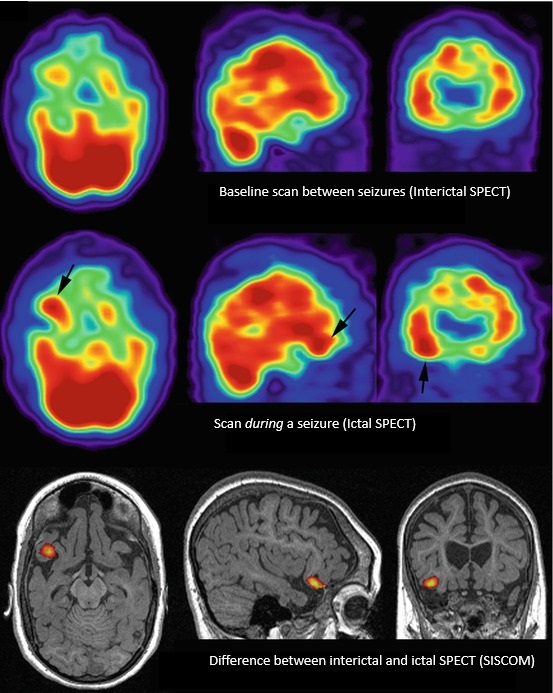

10.1 PET Scan

A PET scan — short for positron emission tomography — measures how active different parts of the brain are by tracking how they use energy. Brain cells need glucose (a type of sugar) to function. Before the scan, a small amount of a mildly radioactive glucose tracer is injected into a vein. The scanner then detects where in the brain that tracer is being used.

In epilepsy, PET is almost always done between seizures, when the brain is in its resting state. The area of the brain responsible for seizures often uses less energy than the surrounding tissue during this resting period, so it shows up as a dimmer, cooler region on the scan. Even when the MRI looks completely normal, a PET scan can sometimes point to the part of the brain where seizures are coming from.

Figure 10.1: Coronal FDG-PET CT scan showing reduced metabolic activity in the left temporal lobe (right side of image), consistent with a seizure focus in that region.1